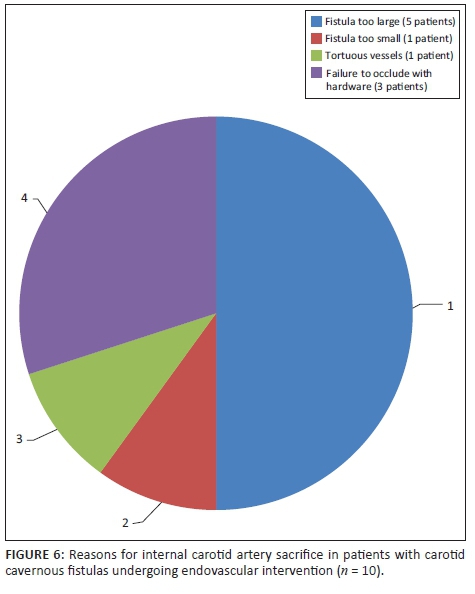

Fistula occlusion was attained via embolisation or trapping in all cases that were compliant with management and in whom intervention was attempted (n = 36, 100%). Sacrifice of the affected ICA was required in 10 patients (27.78%). Reasons for sacrifice are demonstrated in Figure 6. No documented post-procedural complications were noted.

One of the patients presented post-trauma, with bilateral high-flow fistulas. Multiple balloons were deployed bilaterally, which resulted in reduced filling but persistence of the fistula. A repeat angiogram was then performed at a later date. The right fistula, which was smaller, was treated successfully using a covered stent (Jo stent). The left fistula, however, was larger and required sacrifice of the left ICA to occlude the fistula. In Table 3, the relationship between outcome and demographic data, the side of fistula and presence of an aneurysm, respectively, is presented. Sacrifice of the ICA was slightly higher in those who had an intracavernous ICA aneurysm compared to those who did not (37.5% vs. 25%); however, this finding was not statistically significant (p = 0.658). A higher rate of ICA sacrifice was also observed in fistulas on the right side (35.3% vs. 21.1%); this result was also not statistically significant (p = 0.463).

Over the years, worldwide studies have showed varying degrees of success at achieving the ideal outcome. Internal carotid artery preservation rate in reviewed studies ranged between 40% and 84%13,14 and CCF occlusion between 86% and 100%.13,15 To date, scant local data exist to our knowledge. In a single local study, Szkup and Beningfield,16 in their series of 34 cases, documented a preserved parent artery in approximately 53% of their cases and attained occlusion in 91%. Most of the cases requiring sacrifice were because of large tears in the affected vessel generally secondary to trauma. The results at our centre, of occlusion in all (100%) of the cases and a 72.22% ICA preservation, is similar in comparison to the reviewed local and international data.

Spontaneous direct CCFs are commonly secondary to rupture of an intracavernous ICA aneurysm. In our study, 37.5% (n = 3) of patients with such an aneurysm ultimately required sacrifice of their ICA. Although this relationship was not statistically significant, studies suggest that parent artery occlusion is sometimes a necessary choice if first-line methods using detachable balloons or coils fail.17